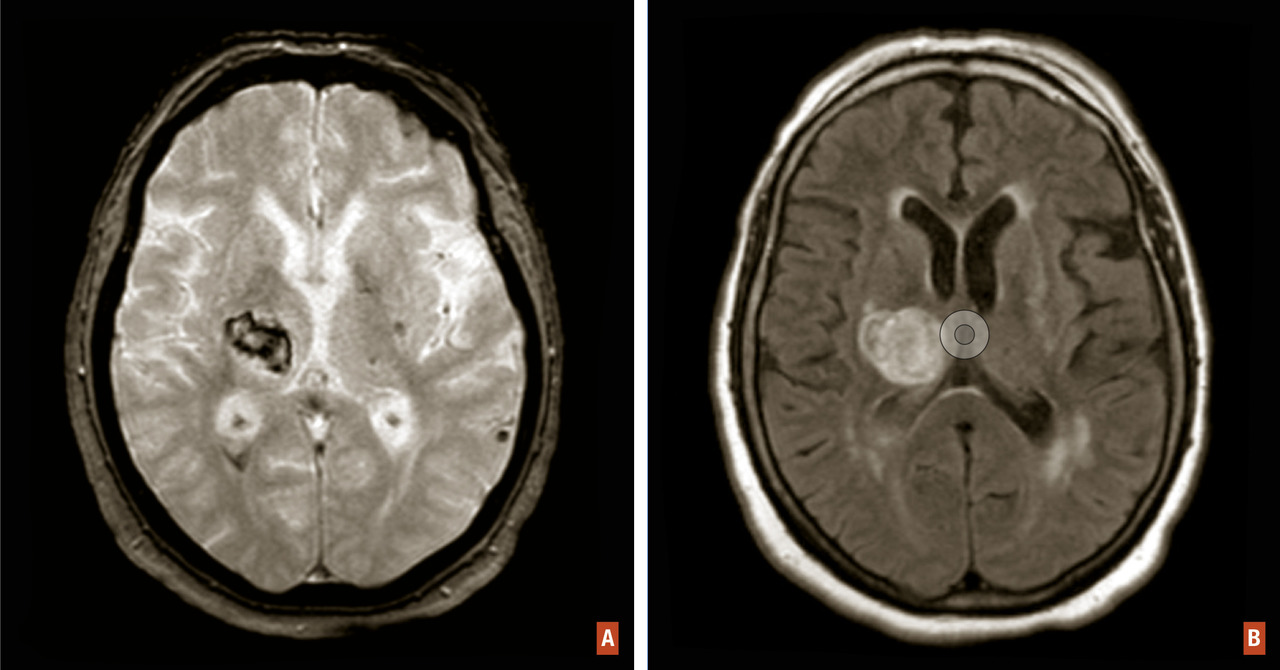

Les hémorragies intracérébrales spontanées résultent d’un saignement cérébral intraparenchymateux en lien avec la rupture de petits vaisseaux généralement touchés par une microangiopathie sporadique. Elles représentent environ 15 % des accidents vasculaires cérébraux (AVC) dans les pays occidentaux. Les hémorragies localisées dans les régions profondes du cerveau sont le résultat de la rupture des petites artérioles touchant préférentiellement le putamen et le thalamus et sont sous-tendues par la microangiopathie des perforantes longues favorisée par les facteurs de risque vasculaires (fig. 1A et B ). Les hémorragies de localisation lobaire proviennent de la rupture d’artérioles de petite et moyenne taille perforant le cortex et la substance blanche sous-corticale et sont principalement sous-tendues chez le sujet âgé par l’angiopathie amyloïde cérébrale (fig. 2 ).